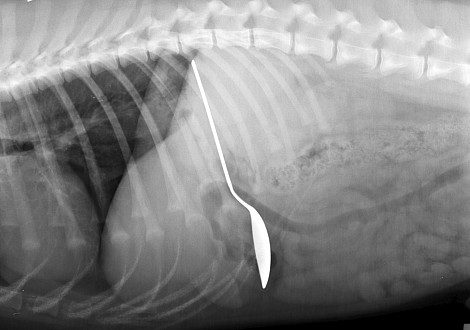

Небольшие предметы из пищевода извлекаются инструментами под местной анестезией. Наиболее точная диагностика наличия инородных тел в желудке и кишечнике животного возможна при проведении рентгенологического исследования.